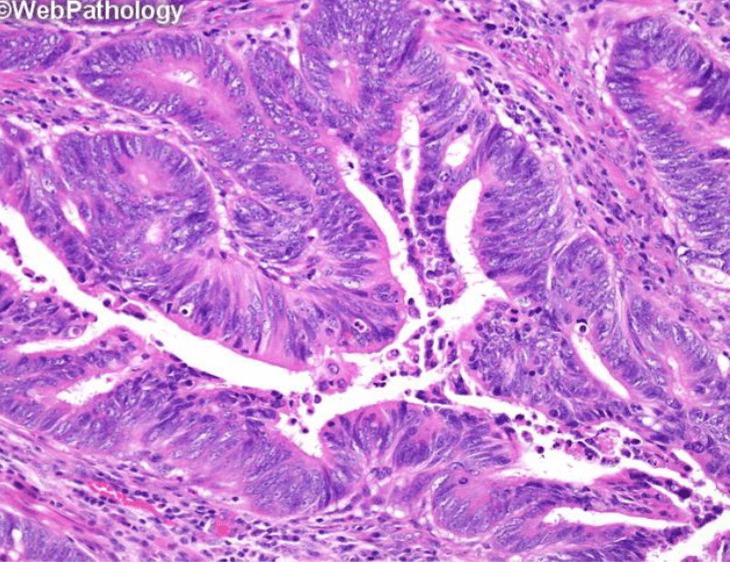

Which image shows malignant colonic mucosa